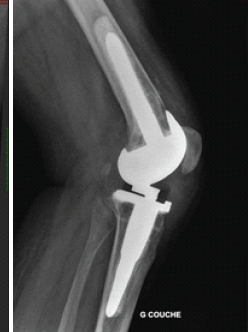

Interest of a V-Y Quadricepsplasty in Bilateral Total Knee Arthroplasty for Ankylosed Flexion Knees in a Patient with Rheumatoid Arthritis – A Case Report

Alphonse Daudet Batchom , Florent Francony , Sekou Sidibe

………………………………p.111-113